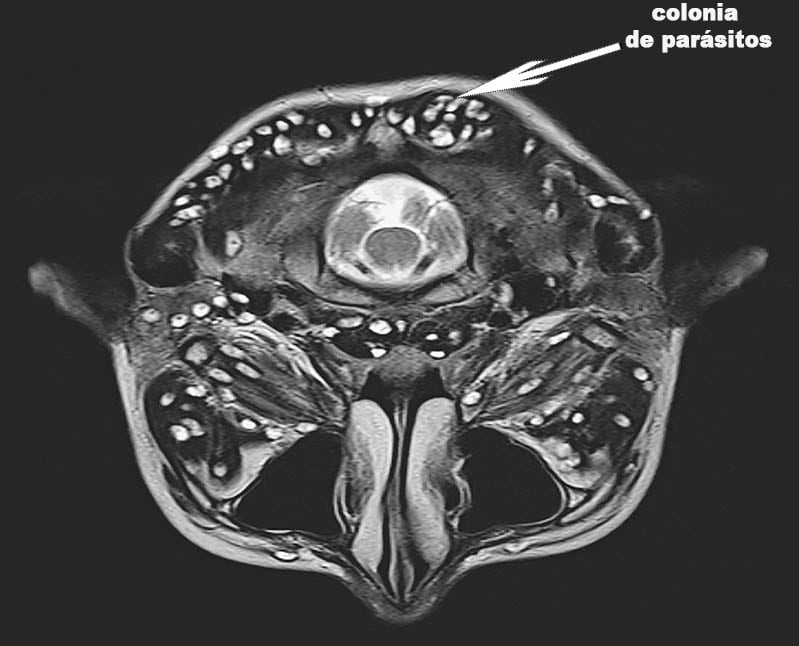

2. Rahim dijangkiti koloni parasit. Malangnya, ia tidak lagi mungkin untuk menyingkirkannya, kerana parasit dan larva mereka telah mengisi rahim pesakit ini sepenuhnya dan meningkatkan bilangan mereka beberapa kali. Oleh itu, ia terpaksa dikeluarkan. Wanita itu diselamatkan. Walau bagaimanapun, keracunan badan sangat teruk sehingga dia terpaksa menjalani rawatan khas selepas pembuangan rahim, dan, malangnya, dia meninggal dunia selepas 3 tahun.

img